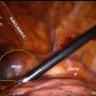

This video demonstrates a technique for laparoscopic repair of a Morgagni hernia, with and without excision of the sac.